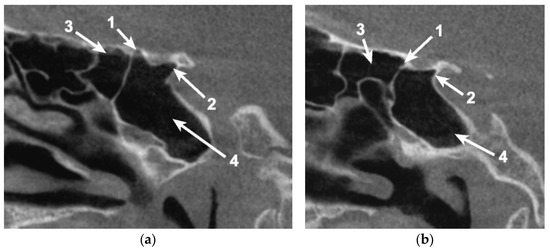

Simultaneous pneumatization of both LSW roots was noted in 31 cases (38.75%) and 43 sides (26.87%) (Table 2; Figure 3). This kind of extensive pneumatization was more frequent in the female group (22 cases, 71%).

Five (16.13%) out of the 31 cases with pneumatization of both LSW roots presented combined pneumatization. If, for the other cases, the origin came either from PEAC (non-ONC/ ONC) or the sphenoid sinus, in these 5 cases, the simultaneous pneumatization occurred from separated origins for each of the two (Figure 3). Two of these patients presented the ONC extending into the OS and the sphenoidal sinus within AR, and the other three cases presented ONC pneumatization extended within the AR and the sphenoidal sinus with a recess within the OS.

Figure 2. Coronal, bilateral three-dimensional volume rendering of the anterior clinoid process (ACP) and sphenoid sinus, posterior view. 1. Pneumatized ACP; 2. Pneumatized optic strut; 3. Pneumatized anterior root; 4. Sphenoid sinus.